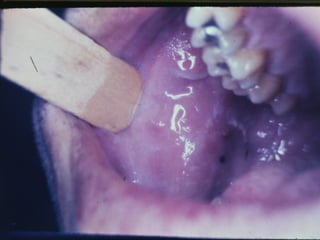

Grânulos de Fordyce

• Etiologia

• Características Clínicas

• Orientação Terapêutica